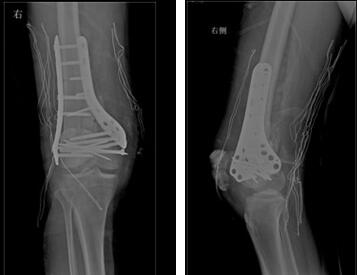

做好术前准备后,王延斌主任及其团队在全麻下为小涛实施“右股骨髁上髁间骨折切开复位内固定术+左跟骨清创负压吸引术”。由于骨折部位结构复杂,粉碎严重,手术难度大。手术从晚上7点到次日的凌晨3点多,手术时间持续约八个小时,顺利完成。

▲术后